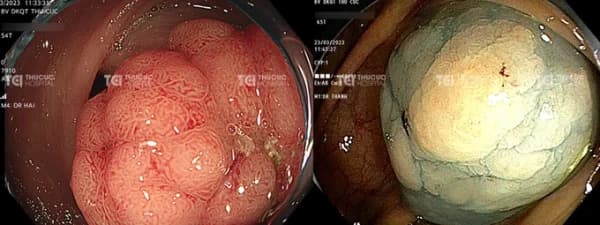

Trường hợp polyp nghịch sản nặng có nguy cơ ác tính cao cần được cắt bỏ qua nội soi.